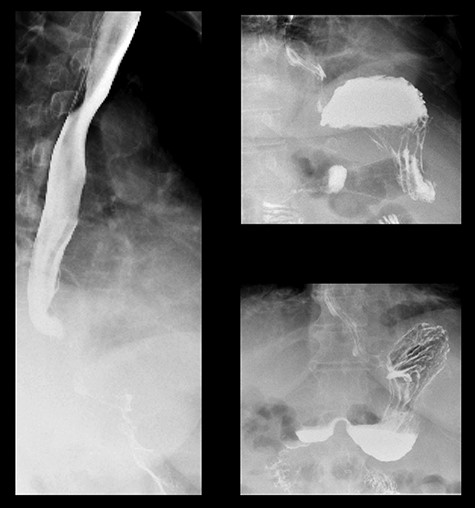

A 59-year-old female presented to the emergency department with a 2-week history of progressive central abdominal pain and distention on a background history of a laparoscopic adjustable band insertion 11 years previously. She had associated nausea, vomiting and denied dysphagia, odynophagia, or change in bowel habit. Clinically, she was afebrile, tachycardic, and on examination, displayed diffuse abdominal tenderness and guarding. Inflammatory markers were mildly elevated (white cell count 13.7 × 109/L, C-reactive protein 105 mg/L), and a moderate hyperlactatemia was observed (lactate 2.4 mmol/L). A plain film abdomen demonstrated a distended, air-filled stomach (Fig. 1). Subsequent computed tomography of the abdomen and pelvis demonstrated an intragastric band erosion with the internalization of the entire gastric band and distal connector tubing within the gastric lumen (Fig. 2). Moderate free fluid and ascites were noted with considerable mesenteric inflammatory fat stranding. The portal vein was non-opacified, indicating a possible portal vein thrombosis (PVT).

The patient was monitored in the intensive care unit postoperatively. A focused hepatic ultrasound was performed, which demonstrated an almost completely thrombosed portal vein. The patient was, therefore, commenced on a therapeutic dose of tinzaparin sodium. The patient required intensive gastroenterology, dietician, physiotherapy and hematology input postoperatively. By 3 weeks, prior to discharge, a barium meal demonstrated normal gastric contours with no filling defects (Fig. 5). No gastric outlet emptying was observed.